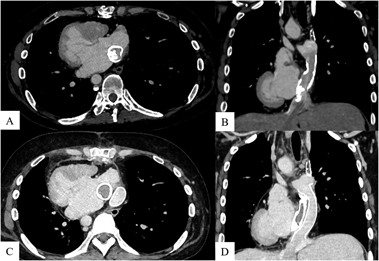

Contrast-enhanced computed tomography (CT) revealed 65% stenosis due to calcification within the intra-atrial conduit (Fig. 1). Blood test results were not indicative of Fontan-associated liver disease; on the other hand, the patient’s brain natriuretic peptide concentration had increased from 72 pg/mL (5 years ago) to 216 pg/mL. The patient was considered a candidate for surgical intervention because of increasing calcification and detectable symptoms.

Fig. 1 Axial and coronal views of CT imaging

A & B: Pre-operative CT shows stenosis due to calcification within the intra-atrial conduit. C & D: Post-operative CT shows no stenosis within the IVC or across the extracardiac conduit. CT, computed tomography; IVC, inferior vena cava

The patient’s condition after the procedure was unremarkable, and her fatigue upon effort decreased rapidly. She was treated with warfarin for postoperative anticoagulation. Postoperative contrast-enhanced CT revealed no stenosis in the IVC or the extracardiac conduit (ECC).